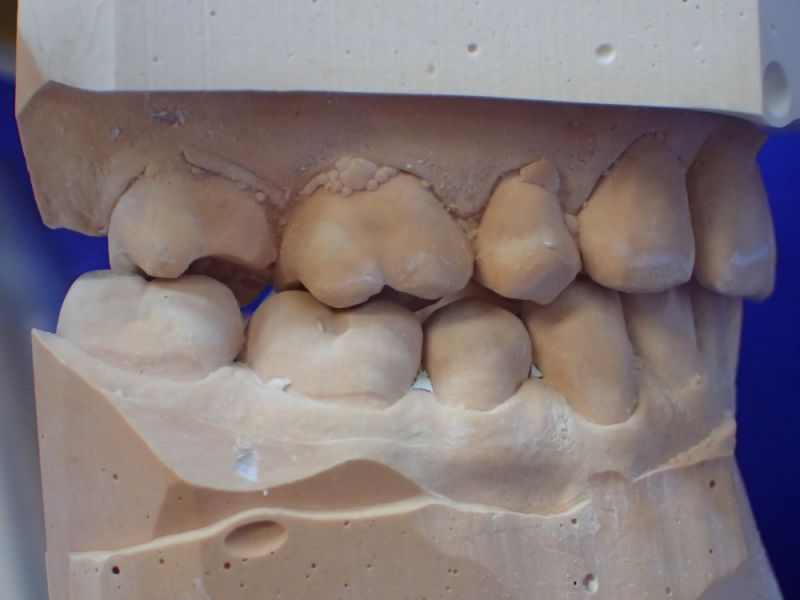

Patientin von der dänischen Grenze erhält einen adjustierten Aufbissbehelf